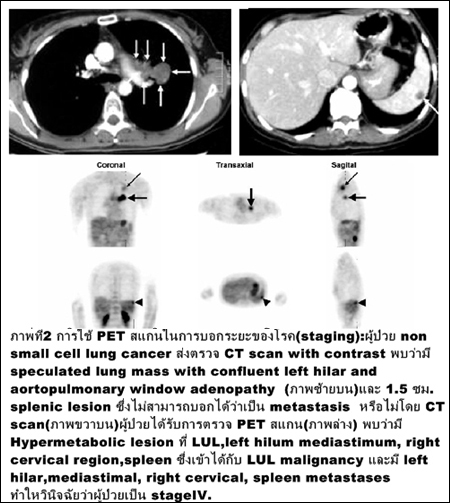

การตรวจหาระยะของโรคมะเร็ง (ภาพที่ 2)